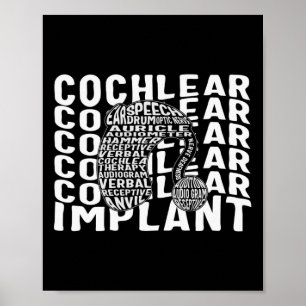

Dövet Cochlear Implant ASL H. Poster

Pris166,00 kr